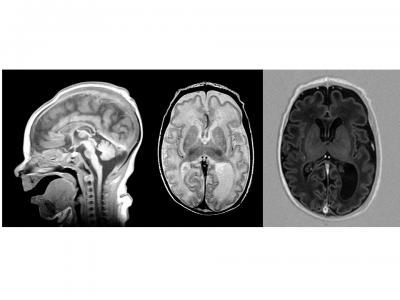

A genetic defect disrupts brain development by affecting the synthesis of asparagine, an amino acid until now thought to be non-essential. The discovery was made by researchers at CHU Sainte-Justine and the University of Montreal. This image shows MRI Images taken from a child who later died from the defect.

Une anomalie génétique perturbe le développement du cerveau en altérant la synthèse de l'asparagine, un acide aminé jugé jusqu'à ce jour non essentiel. Cette découverte a été réalisée par des chercheurs du CHU Sainte-Justine et de l'Université de Montréal. Ces images IRM (MRI) illustrent le cerveau d'un enfant touché par l'anomalie qui décédera par la suite.